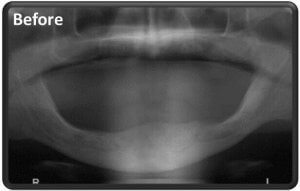

Критическое состояние отсутствия зубов и недостаток челюстной кости в нижней челюсти.